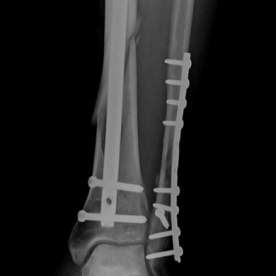

Röntgenbilder